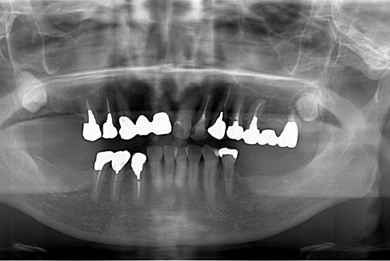

治療内容 インプラント5本(ソケットリフト)、ハイブリッドセラミッククラウン5本

治療部位

6

7 6 6 7

総治療費 1,213,905円

治療期間 7ヶ月

治療前